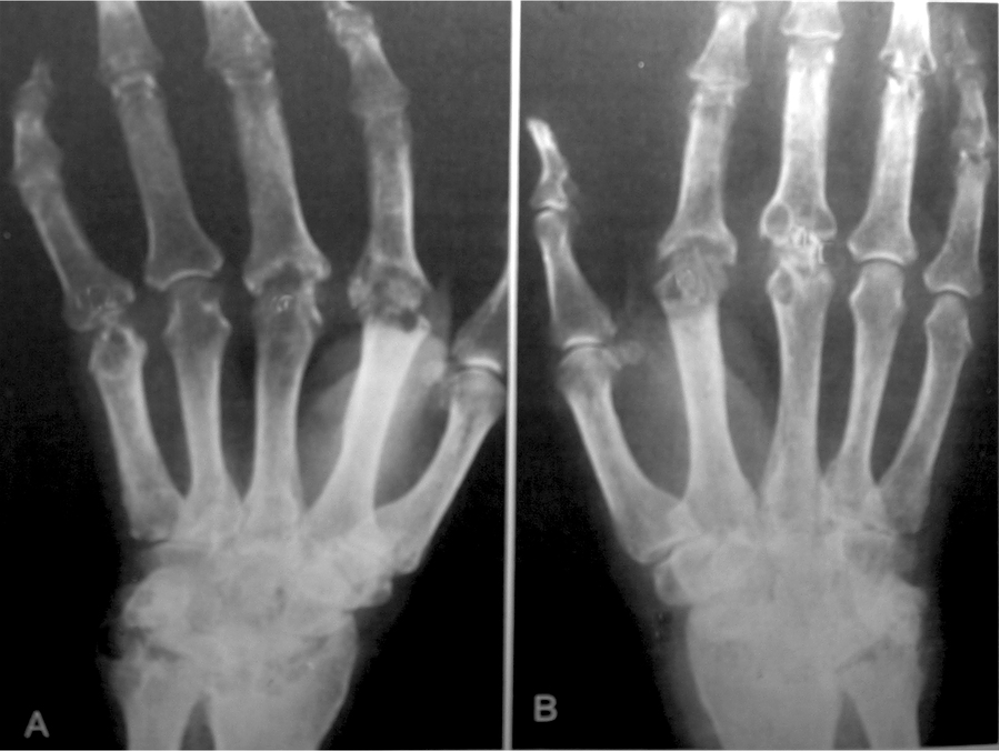

Hình ảnh chung: giai đoạn đầu thấy mất vôi ở đầu xương và cản quang ở phần mềm quanh khớp. Sau một thời gian thấy hẹp khe khớp, hình khuyết xương nhỏ ở đầu xương giữa phần tiếp giáp của phần sụn và đầu xương. Giai đoạn muộn thấy dính 2 đầu xương và biến dạng khớp.

- Giai đoạn I (RA sớm) – Không quan sát thấy những thay đổi phá hủy khi kiểm tra bằng X quang; có thể có loãng xương trên X quang

- Giai đoạn II (tiến triển trung bình) – Bằng chứng chụp X quang về loãng xương quanh khớp, có hoặc không có sự phá hủy xương dưới sụn nhẹ; có thể phá hủy sụn nhẹ, vận động khớp có thể bị hạn chế, nhưng không thấy biến dạng khớp; có teo cơ lân cận; Có thể có tổn thương mô mềm ngoài khớp (ví dụ: nốt dạng thấp và viêm bao gân)

- Giai đoạn III (tiến triển nặng) – Bằng chứng chụp X quang về sự phá hủy sụn và xương cùng với loãng xương quanh khớp; biến dạng khớp (ví dụ, bán trật, lệch trụ, quá duỗi ngón) mà không bị dính khớp; teo cơ rõ; Có thể có tổn thương mô mềm ngoài khớp (ví dụ: nốt dạng thấp, viêm bao gân)

- Giai đoạn IV (tiến triển giai đoạn cuối) – Dính cứng khớp cùng với các tiêu chuẩn của giai đoạn III